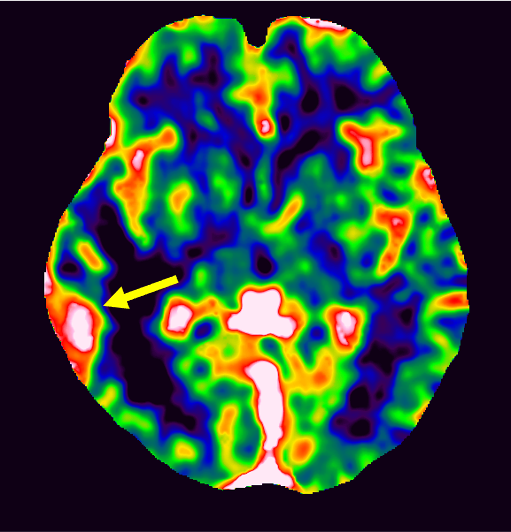

図4.CBV map

同部にCBV上昇あり。